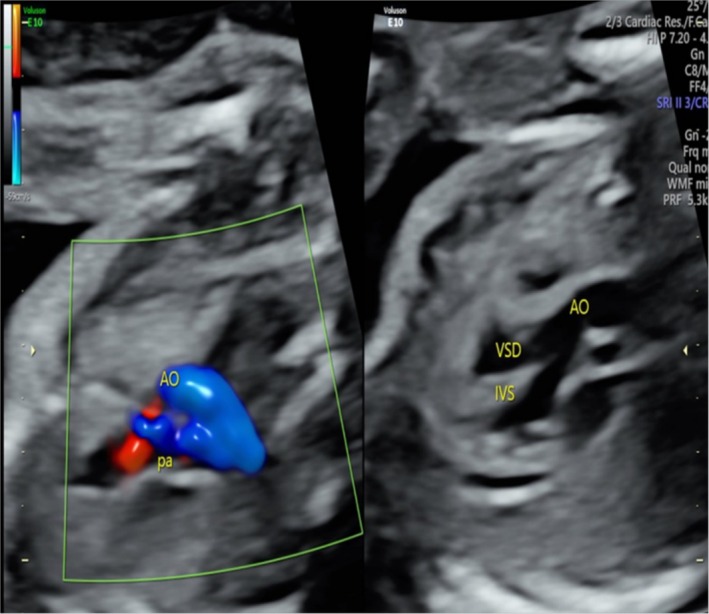

背景:法洛四联症(TOF)是最常见的紫绀型先天性心脏病。然而,我们目前对TOF的遗传病因的了解是有限的。方法:采用全外显子组测序(WES)和Sanger测序对经胎儿产前超声检查诊断为TOF的一家三口进行分析。通过基因分析来确认剪接缺陷。结果:在脑海绵状血管瘤2样(CCM2L)基因中发现了复合杂合变异体,即父本遗传无意义变异体NM_001365692.1:c。741G>A p.(Trp247Ter)和母系遗传剪接位点变异NM_001365692.1:c。1263+2T>A的TOF胎儿表现为室间隔缺损合并覆盖主动脉和肺动脉狭窄。Minigene分析显示,c.1263+2T>A变异导致CCM2L外显子8在RNA剪接过程中发生跳变,这被认为是导致移码和翻译过早终止的原因。这两种变异均未出现在公共人群数据库(Genome Aggregation Database [gnomAD]、1000 Genomes [1000G]、Clinvar)中,并根据ACMG指南(PVS1 + PM2水平证据)被归类为可能致病。结论:据我们所知,这是首次报道的人类CCM2L双等位基因功能丧失变异病例。我们的研究结果表明人类CCM2L与TOF可能存在关联。

Results: We identified compound heterozygous variants in the cerebral cavernous malformation 2-like (CCM2L) gene, namely the paternally inherited nonsense variant NM_001365692.1:c.741G>A p.(Trp247Ter) and the maternally inherited splice-site variant NM_001365692.1:c.1263+2T>A in a fetus with TOF featuring a ventricular septal defect associated with overriding aorta and pulmonary stenosis. Minigene assay showed that the c.1263+2T>A variant led to skipping of CCM2L exon8 during RNA splicing, which is thought to result in frameshift and premature termination of translation. Both variants were absent from the public population databases (Genome Aggregation Database [gnomAD], 1000 Genomes [1000G], Clinvar) and classified as likely pathogenic according to the ACMG guidelines (PVS1 + PM2 level evidence).